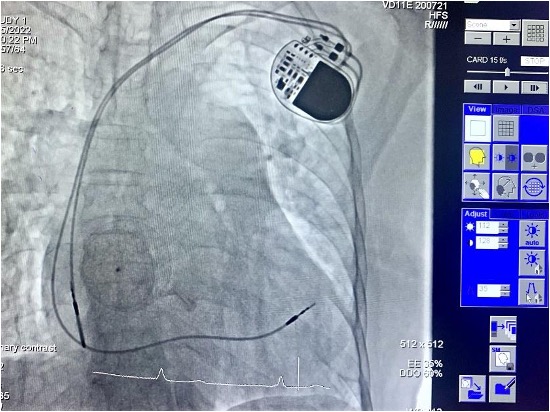

Qua hội chẩn, các bác sĩ quyết định chụp mạch vành cho người bệnh bằng kỹ thuật chụp mạch máu số hóa xóa nền DSA, đo kháng lực phổi, đóng thông liên nhĩ bằng dù qua da và đặt máy tạo nhịp vĩnh viễn, tiến tới ổn định nhịp tim và làm giảm tiến triển suy tim, giảm nguy cơ đột tử, cải thiện sức khỏe cho người bệnh.

Trên trường hợp cụ bà này còn bị thông liên nhĩ, bệnh lý chiếm khoảng từ 5% đến 10% các trường hợp tim bẩm sinh. Đối với các trường hợp thông liên nhĩ không được điều trị triệt để, người bệnh sẽ dần dần có các triệu chứng lâm sàng, lâu dài biểu hiện các dấu hiệu của sự quá tải buồng tim phải như rối loạn nhịp nhĩ (tăng dần nguy cơ theo tuổi của người bệnh), tăng áp động mạch phổi và tăng sức cản mạch phổi, cuối cùng hậu quả tất yếu là dẫn đến suy tim xung huyết. Nếu không điều trị sớm, thông liên nhĩ có thể dẫn đến nhiều biến chứng nguy hiểm, đe dọa tới tính mạng người bệnh. Hiện nay, phương pháp điều trị đang được áp dụng phổ biến cho bệnh lý này là bít lỗ thông liên nhĩ. Thủ thuật bít lỗ thông liên nhĩ là kỹ thuật tương đối phức tạp. Khi được chỉ định thực hiện kỹ thuật này, người bệnh cần tuân thủ đúng mọi hướng dẫn của bác sĩ để giảm nguy cơ tai biến, đảm bảo hiệu quả điều trị bệnh.